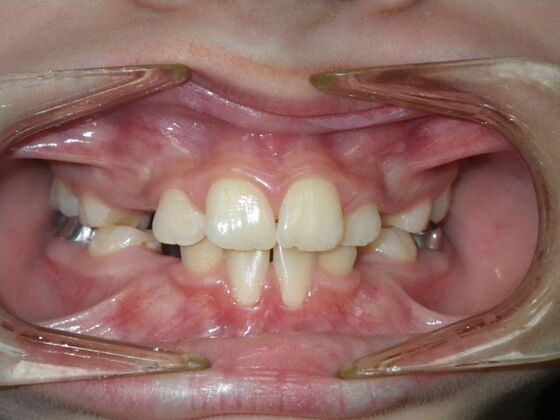

Orthodontics: Case 43

Patient presented with mixed dentition and mild deep overbite, excessive overjet,and rotated lower incisors. She also had a lower bilateral lingual retainer, preventing lower molars from coming forward. She was treated with utility archwires initially, waiting for eruption of cuspids and bicuspids. This was followed by conventional straight wire appliances and upper and lower standard hawley retainers.